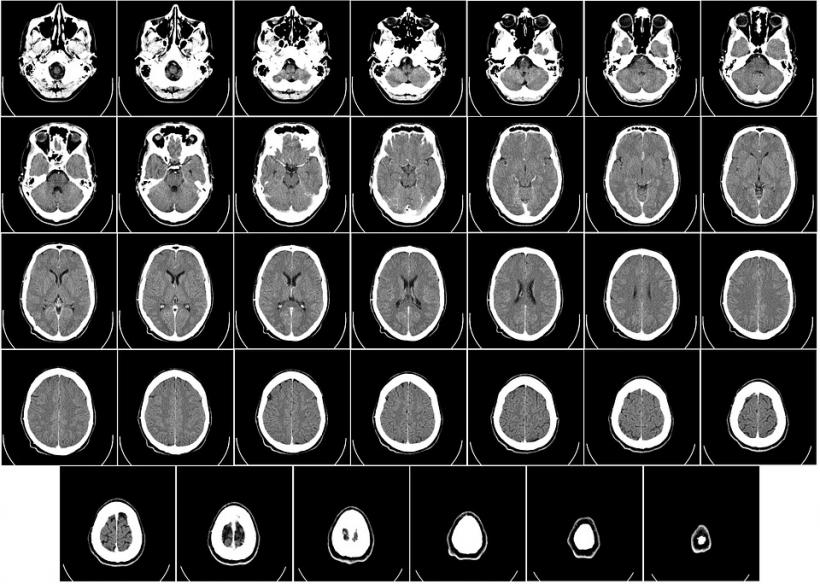

Pentru a ajunge la aceste concluzii, cercetătorii de la Universitatea din Kiel (Germania), au studiat creierul a 56 de adulți, dintre care 23 pedofili bărbați, iar restul bărbați heterosexuali sau homosexuali. În timpul experimentului, creierele subiecților au fost monitorizate cu ajutorul imagisticii prin rezonanță magnetică (RMN), în timp ce acestora le erau prezentate rapid imagini cu bărbați, femei, băieți și fete.

Rezultatele au indicat că la persoanele atrase de adulți de ambele sexe, regiunile creierului asociate cu procesarea fețelor și cu dorința sexuală s-au activat la fețele adulților, în timp ce în cazul pedofililor, aceleași regiuni cerebrale s-au activat la imagini cu chipuri de copii.